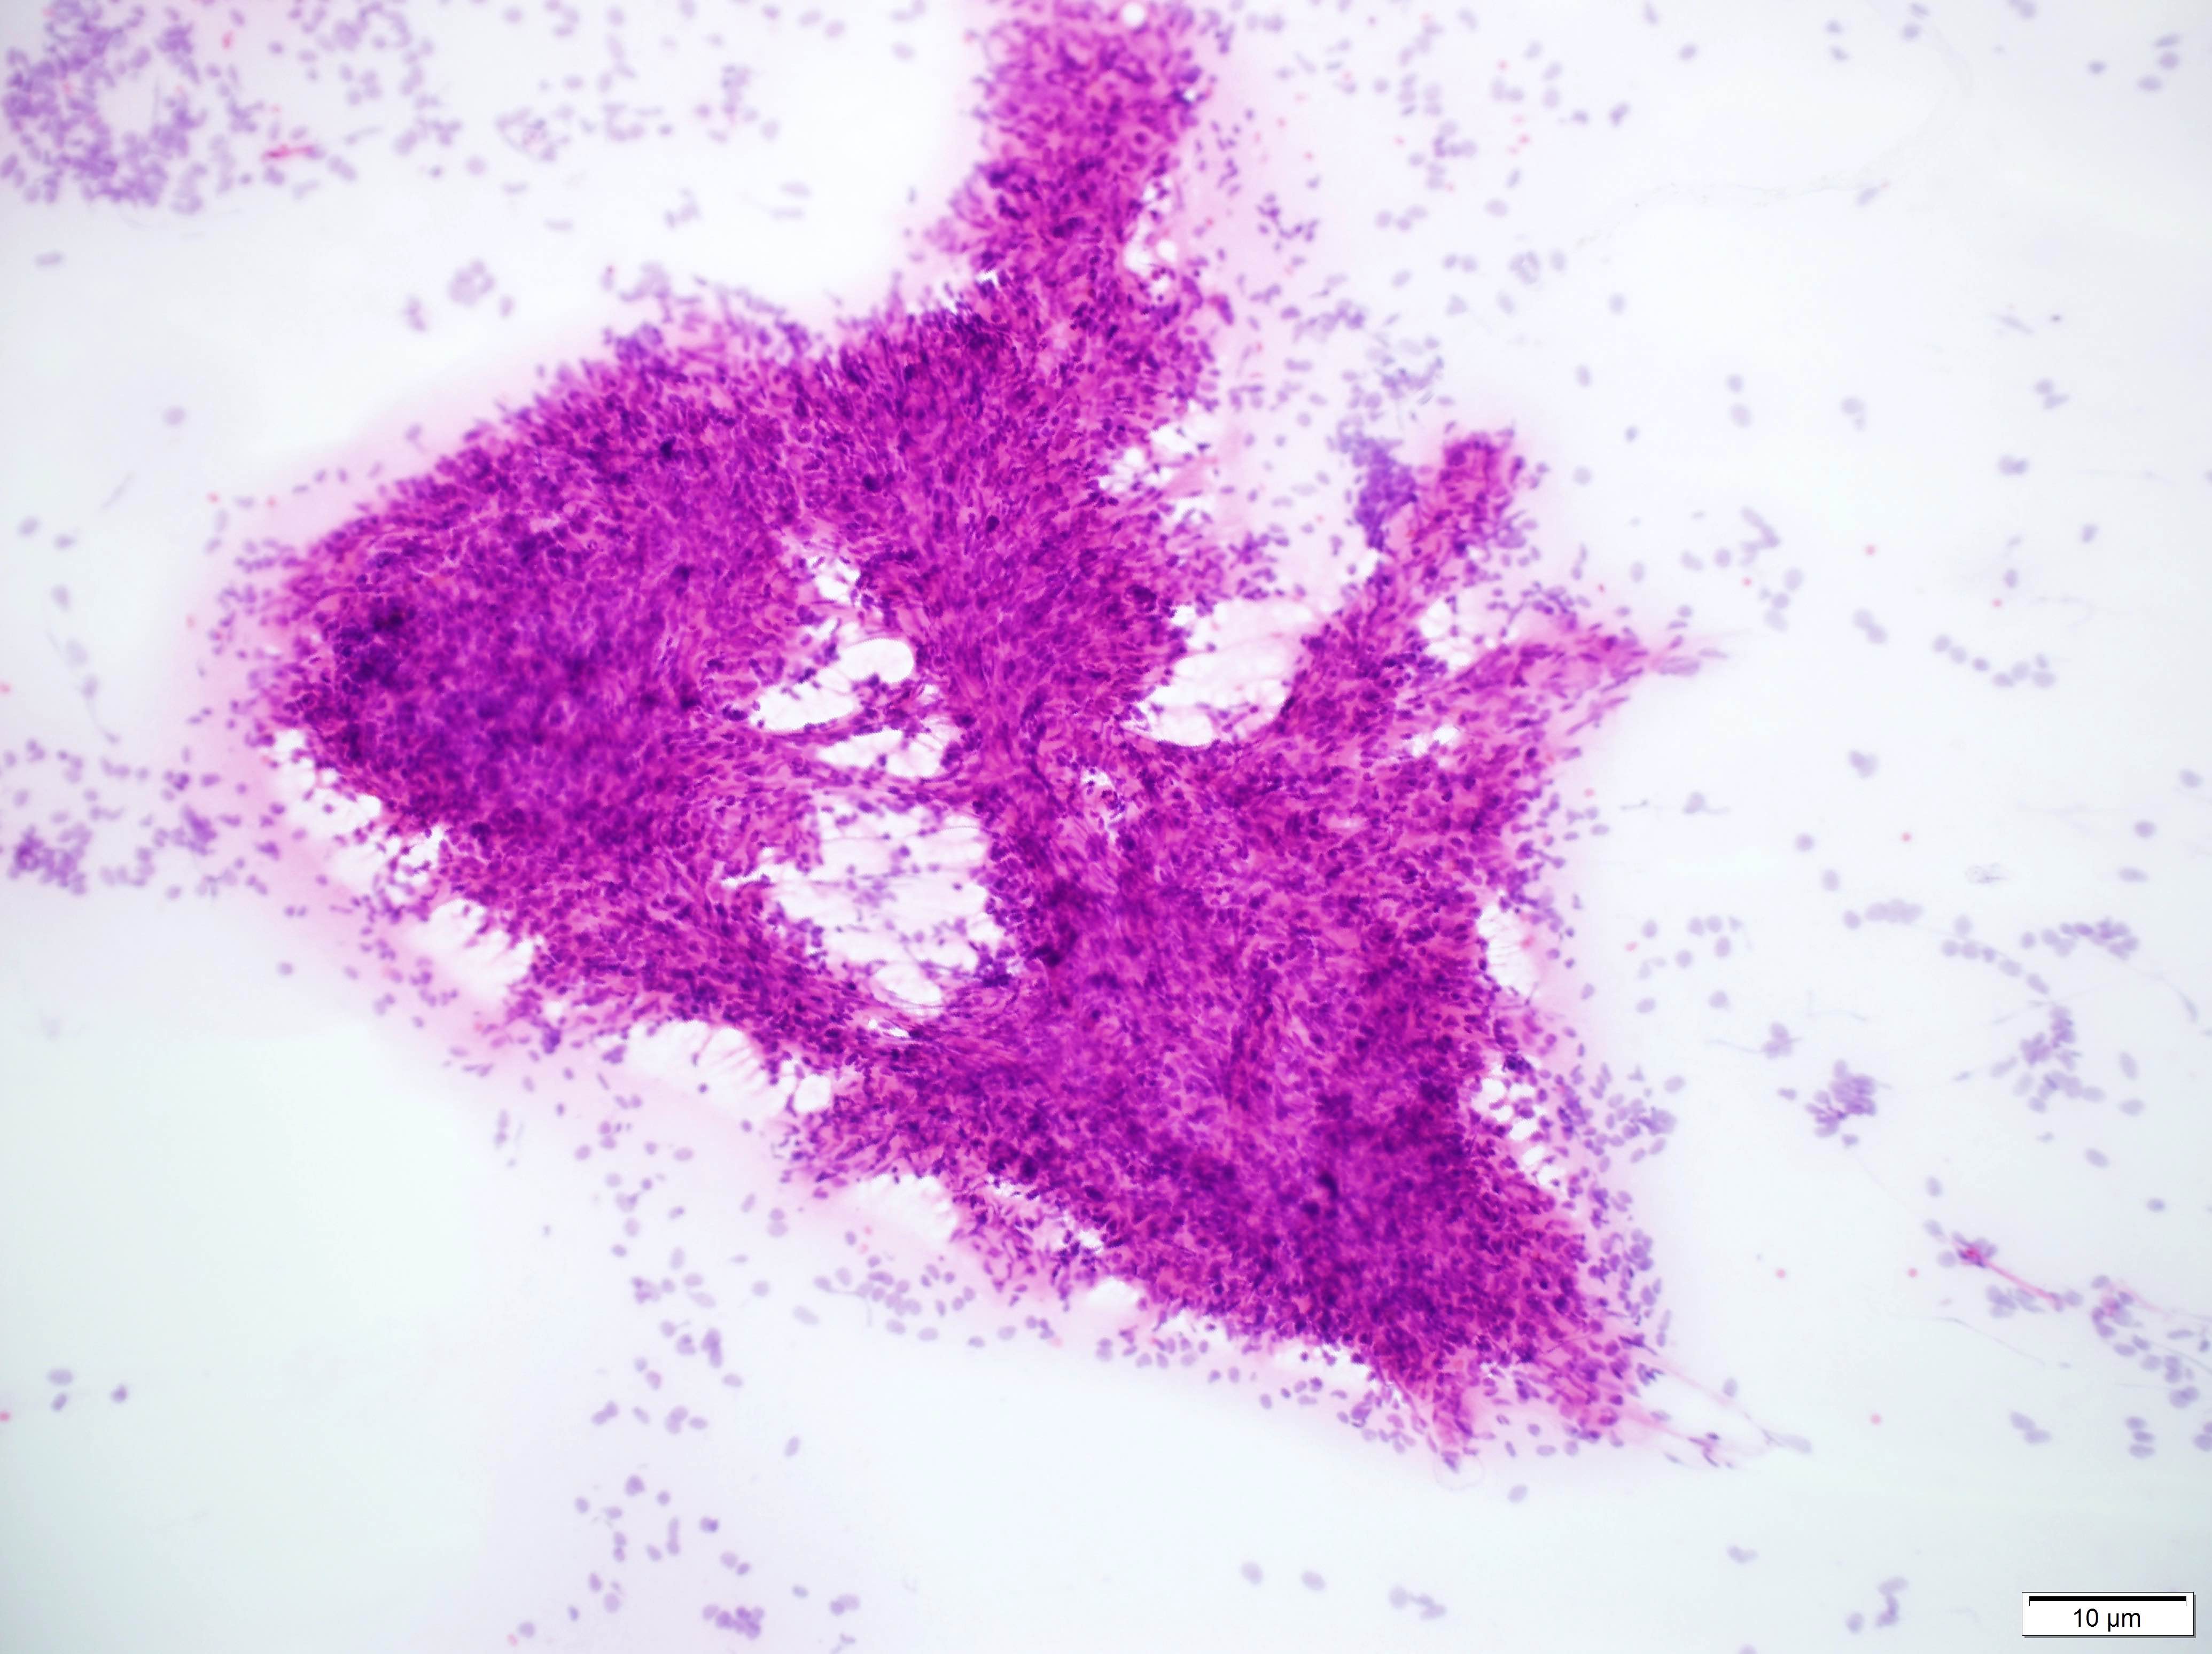

Frozen section description

- Characteristic feature: spindled cells without a single / discrete architecture (patternless pattern)

- Enlarged vascular spaces (staghorn vessels) can suggest SFT

- Typical frozen diagnosis: spindle cell neoplasm, with differential to include SFT, meningioma and possibly other (schwannoma, etc.) depending on location

Intraoperative frozen / smear cytology images

Cytology description

- Lower grade tumors will show the characteristic patternless pattern but there is not a standardized list of cytology criteria for SFT diagnosis (J Pathol Transl Med 2019;53:192)

- Higher grade tumors can show sheets of monotonous cells with heterochromatic nuclei, often with rhabdoid cells and eosinophilic cytoplasm (J Pathol Transl Med 2019;53:192)